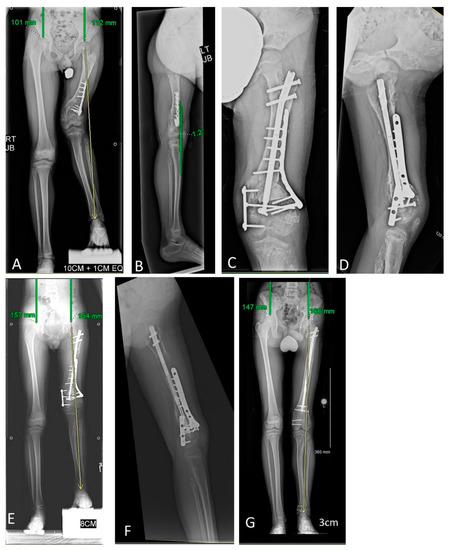

Figure 1. Uncomplicated limb lengthening episode with a motorized intramedullary nail for a patient with enchondromatosis. This figure portrays Patient 6’s lengthening experience. A 9-year-old male with Ollier’s disease affecting his left femur (proximal and distal metaphyseal), tibia (proximal metaphyseal), and fibula (head-neck region). (A) The patient had an initial right > left leg length difference of 76 mm. (B) He was managed with left femur osteotomy and implantable lengthening nail. The proximal and distal cross-locking screws were placed intralesionally. He also had ipsilateral tibia osteotomy and lengthening with a implantable lengthening plate, which is not the focus of the current manuscript. (C) After 75 days, the femur nail had achieved its maximum excursion (50 mm) with corresponding increase in the femur osteotomy gap. Appropriate early regenerate can be observed. This patient had an uncomplicated lengthening experience and is currently consolidating the femur, tibia, and fibula sites.